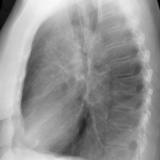

RLL Collapse 2 PA only

Date: 02/28/2004

Views: 3136